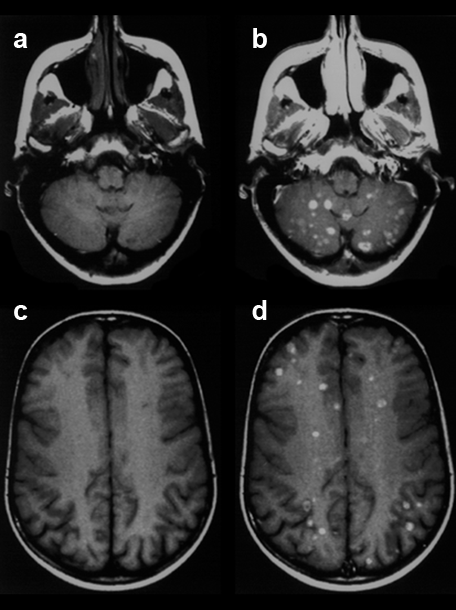

Figure 13-03:

This figure gives an example of a clinical case where finally the application of such a po­si­ti­ve contrast agent helped the diagnostic process and showed the extent of the disease: Patient with breast cancer and recent neurological symptoms. T1-weighted images. The plain MR ima­ges (pre­con­trast: a and c) do not reliably reveal brain lesions. However, the contrast-enhanced MR images (postcontrast: b and d) show a large number of metastases.